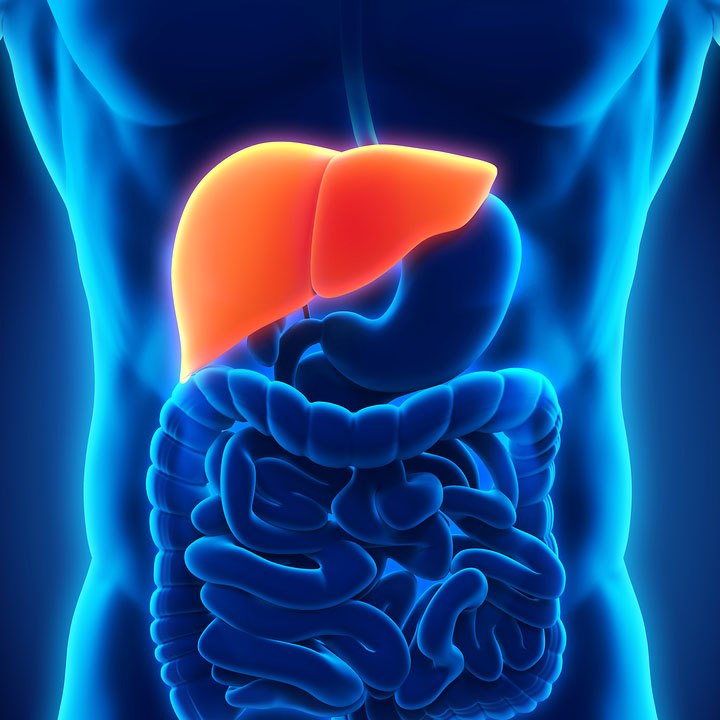

Enlarged liver – Symptoms and causes – Mayo Clinic | Enlarged liver …

Liver | McKay-Dee Gastroenterology Clinic

(1) Liver anatomy- The liver is located in the upper right-hand portion …